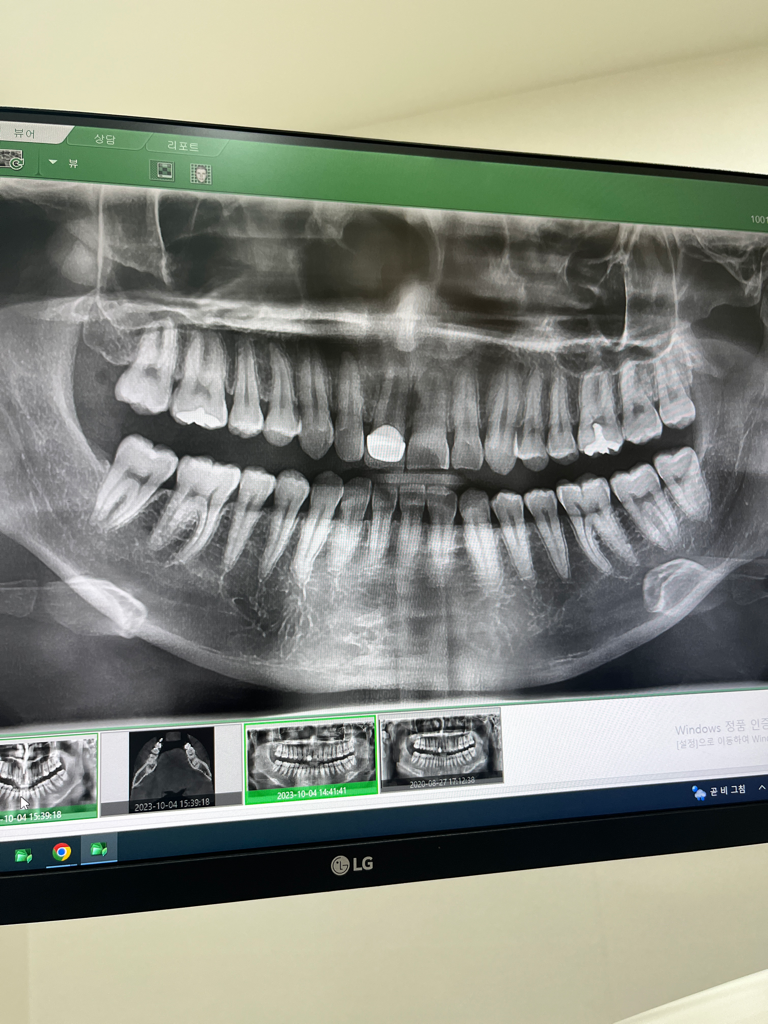

20년전에 앞니가 부러져서 크라운으로 씌웠는데

최근 두달쯤 전부터 크라운 위쪽 잇몸에 고름주머니가

생겼습니다 치과를 가서 ct를 찍어보니 잇몸뼈가 녹고

있어서 당장 발치후 임플란트를 진행 하자고 합니다

심란하네요 ㅠㅠ 전문가분들 부탁드립니다 사진 첨부해요